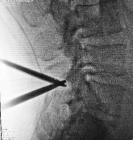

3.微创PKP技术:老年压缩性骨折球囊扩张椎体成形术

经皮球囊扩张椎体后凸成形术是我院很早就开展的一项微创技术,已经有20多年,每年手术约200例,尤其适用于老年骨质疏松引起的胸腰椎骨折;椎体转移性肿瘤(溶骨性破坏);引起疼痛症状的椎体血管瘤、多发性骨髓瘤、Kummell 症。局部麻醉,创伤小恢复快,第二天可以下床活动,迄今为止最高手术患者92岁高龄。